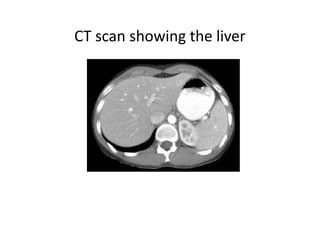

CT scan showing the liver

CT slice through the mid-abdomen

showing multiple normal-appearing organs